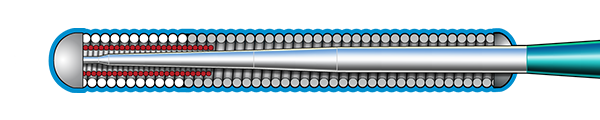

Inner Coil Technology

The advanced design of the stainless steel core and Inner Coil Technology provides a unique combination of exceptional torqueability, rail support, and shape retention.

- Stainless steel inner coil affixed directly to the distal end of the guidewire core

- Improved durability and ease of shaping

- Exceptional torqueability without whipping

Micro EMTTM Technology

MICRO EMT exactly matches the taper of the core and coil, allowing for a lower profile and a more flexible core, leaving almost no room for the core to move within the coil, resulting in 1:1 torque.

- Entry: The smallest tip on the market (0.008”) and the long taper (6 cm) facilitate easy lesion entry in even the most complex lesions.

- Maneuverability: A flexible distal shaft enables excellent intraluminal navigation in complex lesions, with minimal perforation risk.

- Torque: With exactly matched tapers, the core and coil move as one, eliminating whip and empowering precise steerability.